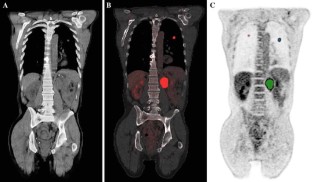

Whole Body Metabolic Tumor Volume and Total Lesion Glycolysis Predict Survival in Patients with Adrenocortical Carcinoma

Adrenocortical carcinoma (ACC) is a rare but lethal malignancy with few reliable prognostic markers. FDG-PET metabolic parameters have been shown to predict survival in several cancers. The objective was to determine if metabolic tumor volume (MTV), total lesion glycolysis (TLG), and maximum standardized uptake value (SUVmax) could serve as prognostic markers in patients with ACC.

A total of 30 patients with ACC prospectively underwent 18F-FDG PET/CT prior to treatment. Whole body MTV, TLG, and SUVmax were measured by a semiautomatic method. A median cutoff was used to determine an association with overall survival (OS) from the time of 18F-FDG PET/CT by the Kaplan–Meier method.

Patients with high whole body MTV (>87.0 mL),TLG (>229.4 SUVlbm*mL), or SUVmax (>8.9 SUV) had a worse OS compared with those with low whole body MTV (median OS, 24 vs 45.1 months, p < .01), TLG (median OS, 24 vs 40.3 months, p < .005), or SUVmax (median OS, 23.7 vs 35.5 months, p < .02). In patients who had operable disease (n = 23), high whole body MTV (>87.0 mL) and TLG (>229.4 SUVlbm*mL) had a worse OS compared with those with low whole body MTV (median OS, 25.1 vs 45.1 months, p < .05) and TLG (median OS, 25.1 vs 40.3 months, p < .05), but a high SUVmax (>8.9 SUV) was not associated with worse OS (p = .11).

Patients with ACC and a high whole body MTV, TLG, and SUVmax have a worse prognosis and OS. Measurement of whole body MTV and TLG may be helpful for guiding therapy for patients with ACC.